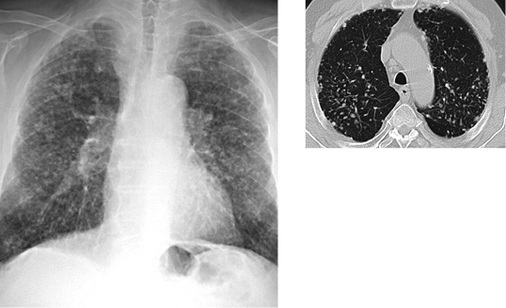

Die Schwielen sind häufig hantelförmig konfiguriert und ordnen sich bevorzugt bilateral parallel zur Thoraxwand in den Oberfeldern dorsal der Trachealebene an. Gelegentlich treten Schwielen auch im Mittel- und Unterlappen auf. Die rechte Lunge ist etwas häufiger betroffen. Im weiteren Verlauf kann es zu einer Schwielenwanderung kommen (Bohlig 1988) (  Abb. 6a ), im unkomplizierten Verlauf wandern die Schwielen in Richtung Hilus, bei begleitenden parenchymalen Narben kann auch eine Wanderung der Schwiele nach peripher mit Distraktion der Hilusstrukturen erfolgen. Die von den Hiluslymphknoten ausgehende Verschwielung kann zu Verziehungen der Gefäße und Bronchien auch mit Bronchiektasen führen. Die Bronchiallumina können eingeengt werden, in fortgeschrittenen Fällen können Bronchialverschlüsse mit angrenzenden Atelektasen besonders im Mittellappen auftreten. Differenzialdiagnostische Schwierigkeiten bestehen in der Abgrenzung von nekrobiotischen Einschmelzungen dieser Schwielen gegenüber silikotuberkulösen Kavernen und zentral einschmelzenden Lungenkarzinomen (Barboza et al. 2008; Chong et al. 2006).

Bei Arbeitern in afrikanischen Goldminen wird ein gegenüber der Normalpopulation 2,8fach erhöhtes Risiko, an Tuberkulose zu erkranken, beobachtet (Cowie 1994). Die Tuberkulose kann präexistent sein und exazerbieren, kann sich aber auch in einer vorbestehenden Silikose entwickeln. Auch bei der Infektion mit atypischen Mykobakterien kann das klinische und radiologische Bild der Silikotuberkulose auftreten. Bei morphologisch ähnlichen Befunden zwischen Silikose und Tuberkulose ist insbesondere der Vergleich mit Voruntersuchungen von eminenter Bedeutung. Finden sich neu aufgetretene Tree-in-bud-Phänomene, schnell zunehmende asymmetrisch ausgeprägte Noduli oder Konsolidierungen, insbesondere mit Einschmelzungen, ist differenzialdiagnostisch an eine floride Silikotuberkulose zu denken (Barboza et al. 2008; Martins et al. 2010) (  Abb. 6b ).